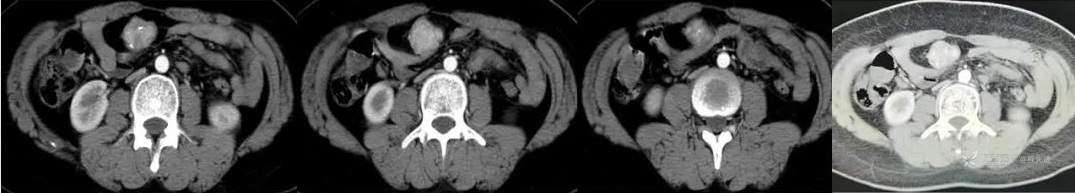

CT

图像依次为平扫(CT值46HU),动脉期(CT值138HU),静脉期(CT值137HU),延时期(CT值96HU)斜矢状位重建